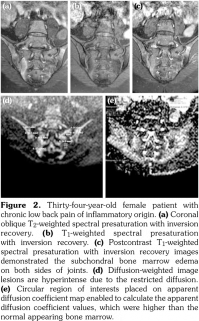

Sacroiliac joints were assessed according to ankylosing spondylitis criteria. Before evaluation of standard MRI protocol, patients’ information was removed from images. Afterwards, two experienced radiologists evaluated the images for the presence of inflammatory activity twice at separate sessions to assess interobserver variability. Following the examination of T2-weighted SPIR, contrast- enhanced T1-weighted SPIR, and DWIs at b values of 600 s/mm2, two radiologists and rheumatologists reached a consensus on the disease activity in the light of positive features of Berlin criteria. The DWIs were transferred to a separate workstation (Phillips, Extended MR workspace, 2.6.3.2.HF3, Netherlands). ADC maps were generated. T2-weighted SPIR images, contrast-enhanced images and diffusion-weighted images with ADC maps were put on the screen side by side. In the disease group, the hyperintense lesions on T2-weighted SPIR images and enhanced focuses on contrast- enhanced images were noted and the same lesions were marked on DWI images and ADC map. A circular ROI with a range of 40-75 mm2 was placed in those areas. In the control group a circular ROI was placed in the subarticular area of joints. Also, the same process was performed for the normal-appearing bone marrow areas near the joints of the disease group (Figure 2). Four standard measurements were conducted from each joint, including two on sacral and the other two on the iliac side for all patients (Figure 3). Additionally, two measurements were conducted from the fifth lumbar vertebra and one from each iliac wing (Figure 4). All measurements were performed twice. ADC values were expressed as square millimeters per second. The r-ADC ratio was calculated by dividing ADC value of subchondral bone or inflammatory lesions to ADC values of the fifth lumbar vertebra and iliac wings.